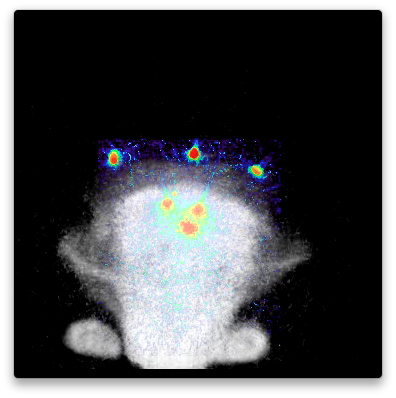

A natural stroke model in rabbits, in routine use in the laboratory Dr. Culp at UAMS, has been used for research into stroke progression and treatment. By addition of imaging to this model, the detailed progression of treatment of stroke has been measured. Clots formed from the rabbit’s blood were radiolabeled by 3D Imaging with F-18 (I-124 and Zr-89 labeling is equally possible, as well as labeling for SPECT with I-125 or I-123, or even fluorescent labeling; but the use of PET allowed quantitative measurement of clot dissipation during a two hour period including treatment.). The radiolabeled blood clots were used by Dr. Culp’s lab to create a natural stroke which was then treated. PET imaging before, during, and after treatment established that the clots were stable without treatment, degraded during treatment, and continued to degrade after treatment. These videos show the progression. In some only the PET scans are shown, so only the clots are visible, but are easily located and quantified. In others, an overlay of an FDG image is used to show the loacation of the brain and other soft tissues.

Videos show the field of view as it evolves in time, and with rotation to help visualize the 3D data and relative positions of the clots. Click on image to download and view the Videos.